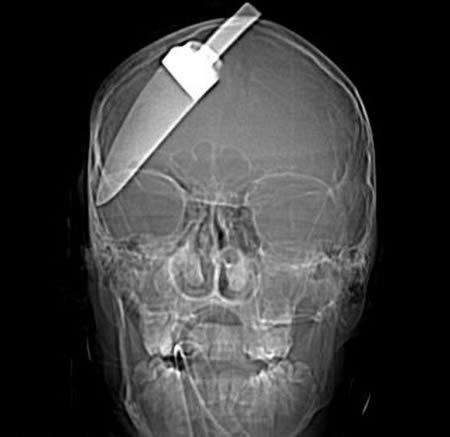

Дэлхийн хаана болсон хэрэг гэдэг нь одоогоор тодорхойгүй байна. Цэргийн нууц болохоор цаг нь болохоор хаана гэдэг нь илрэх биз ээ. Нэгэн тулааны үеэр хамгийн “идэвхтэй” байсан цэргийн толгойн тус газар хутга зоосон явдал гарчээ. Тухайн үед тархиндаа гэмтэл авсан цэргийг амьд гарна гэж хэн ч таамаглаагүй бөгөөд мөн л мэс заслын ачаар хөл дээрээ зогссон байна.

Энэ тэнэг залууг хараад байгаарай. 19-хөн настай хэрнээ өөрийгөө “туршиж” тархиндаа үйлний хайч зоосон байгаа юм. Энэ хэрэг манай хойд хөршийн Екатринбург хотноо болсон. Толгойндоо хайч зоогч эрийг Марк Макаренков гэдэг бөгөөд найз охинтойгоо муудалцсан уурандаа амиа хорлохоор тархиндаа хайч зоосон ч бүтэлгүй оролдлого болжээ. Түүний ээж цаг алдалгүй түргэн дуудаж, яаралтай хагалгаанд оруулсан байна. Хайч залуугийн гавланд 5см гүн орсон бөгөөд хараа, тархинд нь сөрөг нөлөө үзүүлээгүй байна. Залууг амиа хорлох оролдлого хийснийг дуулсан найз охин нь эргэн ирсэн бөгөөд өдгөө аз жаргалтай амьдарч байгаа гэсэн.